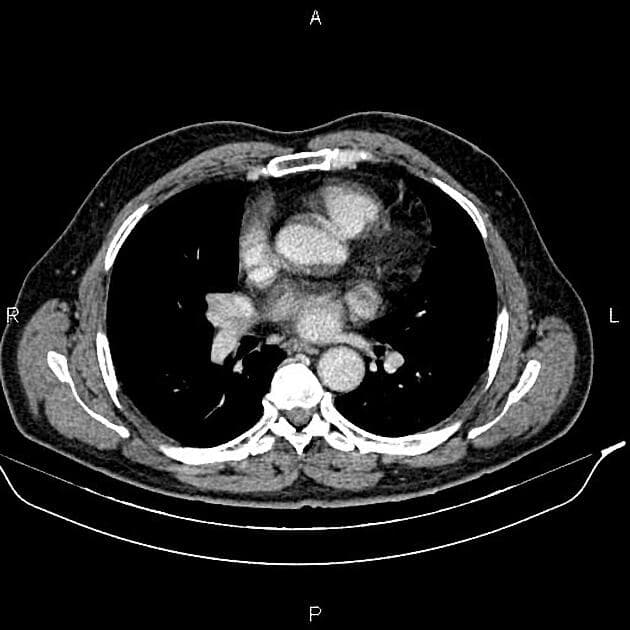

- Một khối nang khu trú một phần lồi ra ngoài (exophytic) kích thước 48 mm, thành dày ngấm thuốc (enhancement) và có các vách ngăn cùng các nốt ngấm thuốc lệch tâm (eccentric enhancing nodules) được ghi nhận ở phần giữa của thận phải.

- Một vài mạch máu tuần hoàn bàng hệ (collateral circulation) nhỏ giãn được ghi nhận trong khoảng gian thận (perinephric space).

Khối nang thận - phân loại Bosniak IV (Renal cystic mass - Bosniak class IV)

- "Các đặc điểm hình ảnh chính bao gồm thành dày ngấm thuốc, vách ngăn ngấm thuốc và các nốt ngấm thuốc lệch tâm."